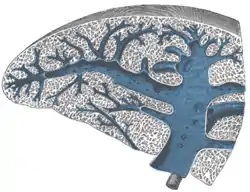

Transverse section of the spleen, showing the trabecular tissue and the splenic vein and its tributaries

Transverse section of the spleen, showing the trabecular tissue and the splenic vein and its tributaries Spleen